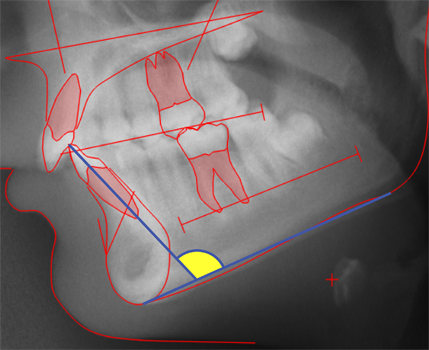

CEPHALOMETRIC MORPHOLOGICAL ANALYSIS

The illustations on this introduction page are discussed in detail in:

Cephalometric Morphological Analysis Parameters

Jens Bjoern-Joergensen, DDS, TIOPS ApS, Roskilde, Denmark

Ib Leth Nielsen, DDS, Division of Orthodontics, University of California, San Francisco

Example of variable values calculation sheet